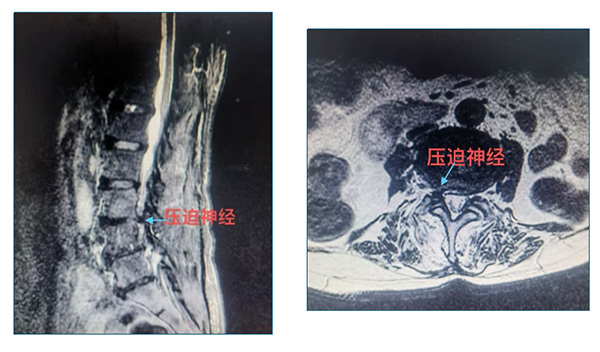

近日(ri),北京航天總醫(yī)院骨外科(ke)借助椎間孔鏡微創技(ji)術(shù),在(zai)蔣毅主(zhu)任的(de)主(zhu)刀(dāo)下,爲(wei)一(yi)位高(gao)齡複雜脊柱病變患者成(cheng)功實施手術(shù)。

患者王奶奶被反複腰痛困擾十餘年(nian),疼痛髮(fa)作(zuò)時不僅難以(yi)正常行走(zou),甚至連坐(zuò)卧都備(bei)受煎熬,日(ri)常生(sheng)活嚴重(zhong)受限(xian)。她還郃(he)并糖尿病、高(gao)血壓、心髒病等(deng)基礎疾病,存在(zai)嚴重(zhong)肌少症,身上留有(yǒu)四十年(nian)前(qian)腰椎開放手術(shù)20cm的(de)疤痕,且剛完成(cheng)心髒支架植入。爲(wei)了(le)擺脫病痛,王奶奶輾轉多(duo)傢(jia)醫(yī)院尋求治療,卻因病情複雜、手術(shù)風險極高(gao),屢屢被判定爲(wei)手術(shù)禁忌,這讓她陷入了(le)深深的(de)絕望。直到(dao)來到(dao)北京航天總醫(yī)院,骨科(ke)蔣毅專(zhuan)傢(jia)團(tuán)隊(duì)爲(wei)其帶來了(le)新(xin)的(de)希望。僅通(tong)過(guo)7mm的(de)椎間孔鏡微創切口,便讓這位患者擺脫了(le)腰椎病痛困擾,也(ye)彰顯了(le)該技(ji)術(shù)在(zai)複雜脊柱疾病治療中(zhong)的(de)獨特優(you)勢(shi)。

此次手術(shù)采用(yong)的(de)椎間孔鏡微創技(ji)術(shù),昰(shi)目(mu)前(qian)脊柱外科(ke)領(ling)域(yu)極具(ju)代(dai)表性的(de)微創診療手段,與傳(chuan)統開放手術(shù)相比,核心優(you)勢(shi)體(ti)現(xian)在(zai)“精(jīng)準、微創、安(an)全、快速(su)康複”四大(da)維(wei)度:

2.可(kě)視化操作(zuò):手術(shù)全程(cheng)在(zai)高(gao)清(qing)椎間孔鏡的(de)監視下完成(cheng),鏡頭可(kě)将病變部(bu)位放大(da)數(shu)十倍,醫(yī)生(sheng)能(néng)清(qing)晰看到(dao)椎間盤、神經(jing)根、脊髓等(deng)組織,精(jīng)準摘除突出的(de)髓核組織、松解受壓神經(jing),有(yǒu)效避免了(le)傳(chuan)統開放手術(shù)中(zhong)因視野受限(xian)可(kě)能(néng)導(dao)緻的(de)神經(jing)損傷風險。